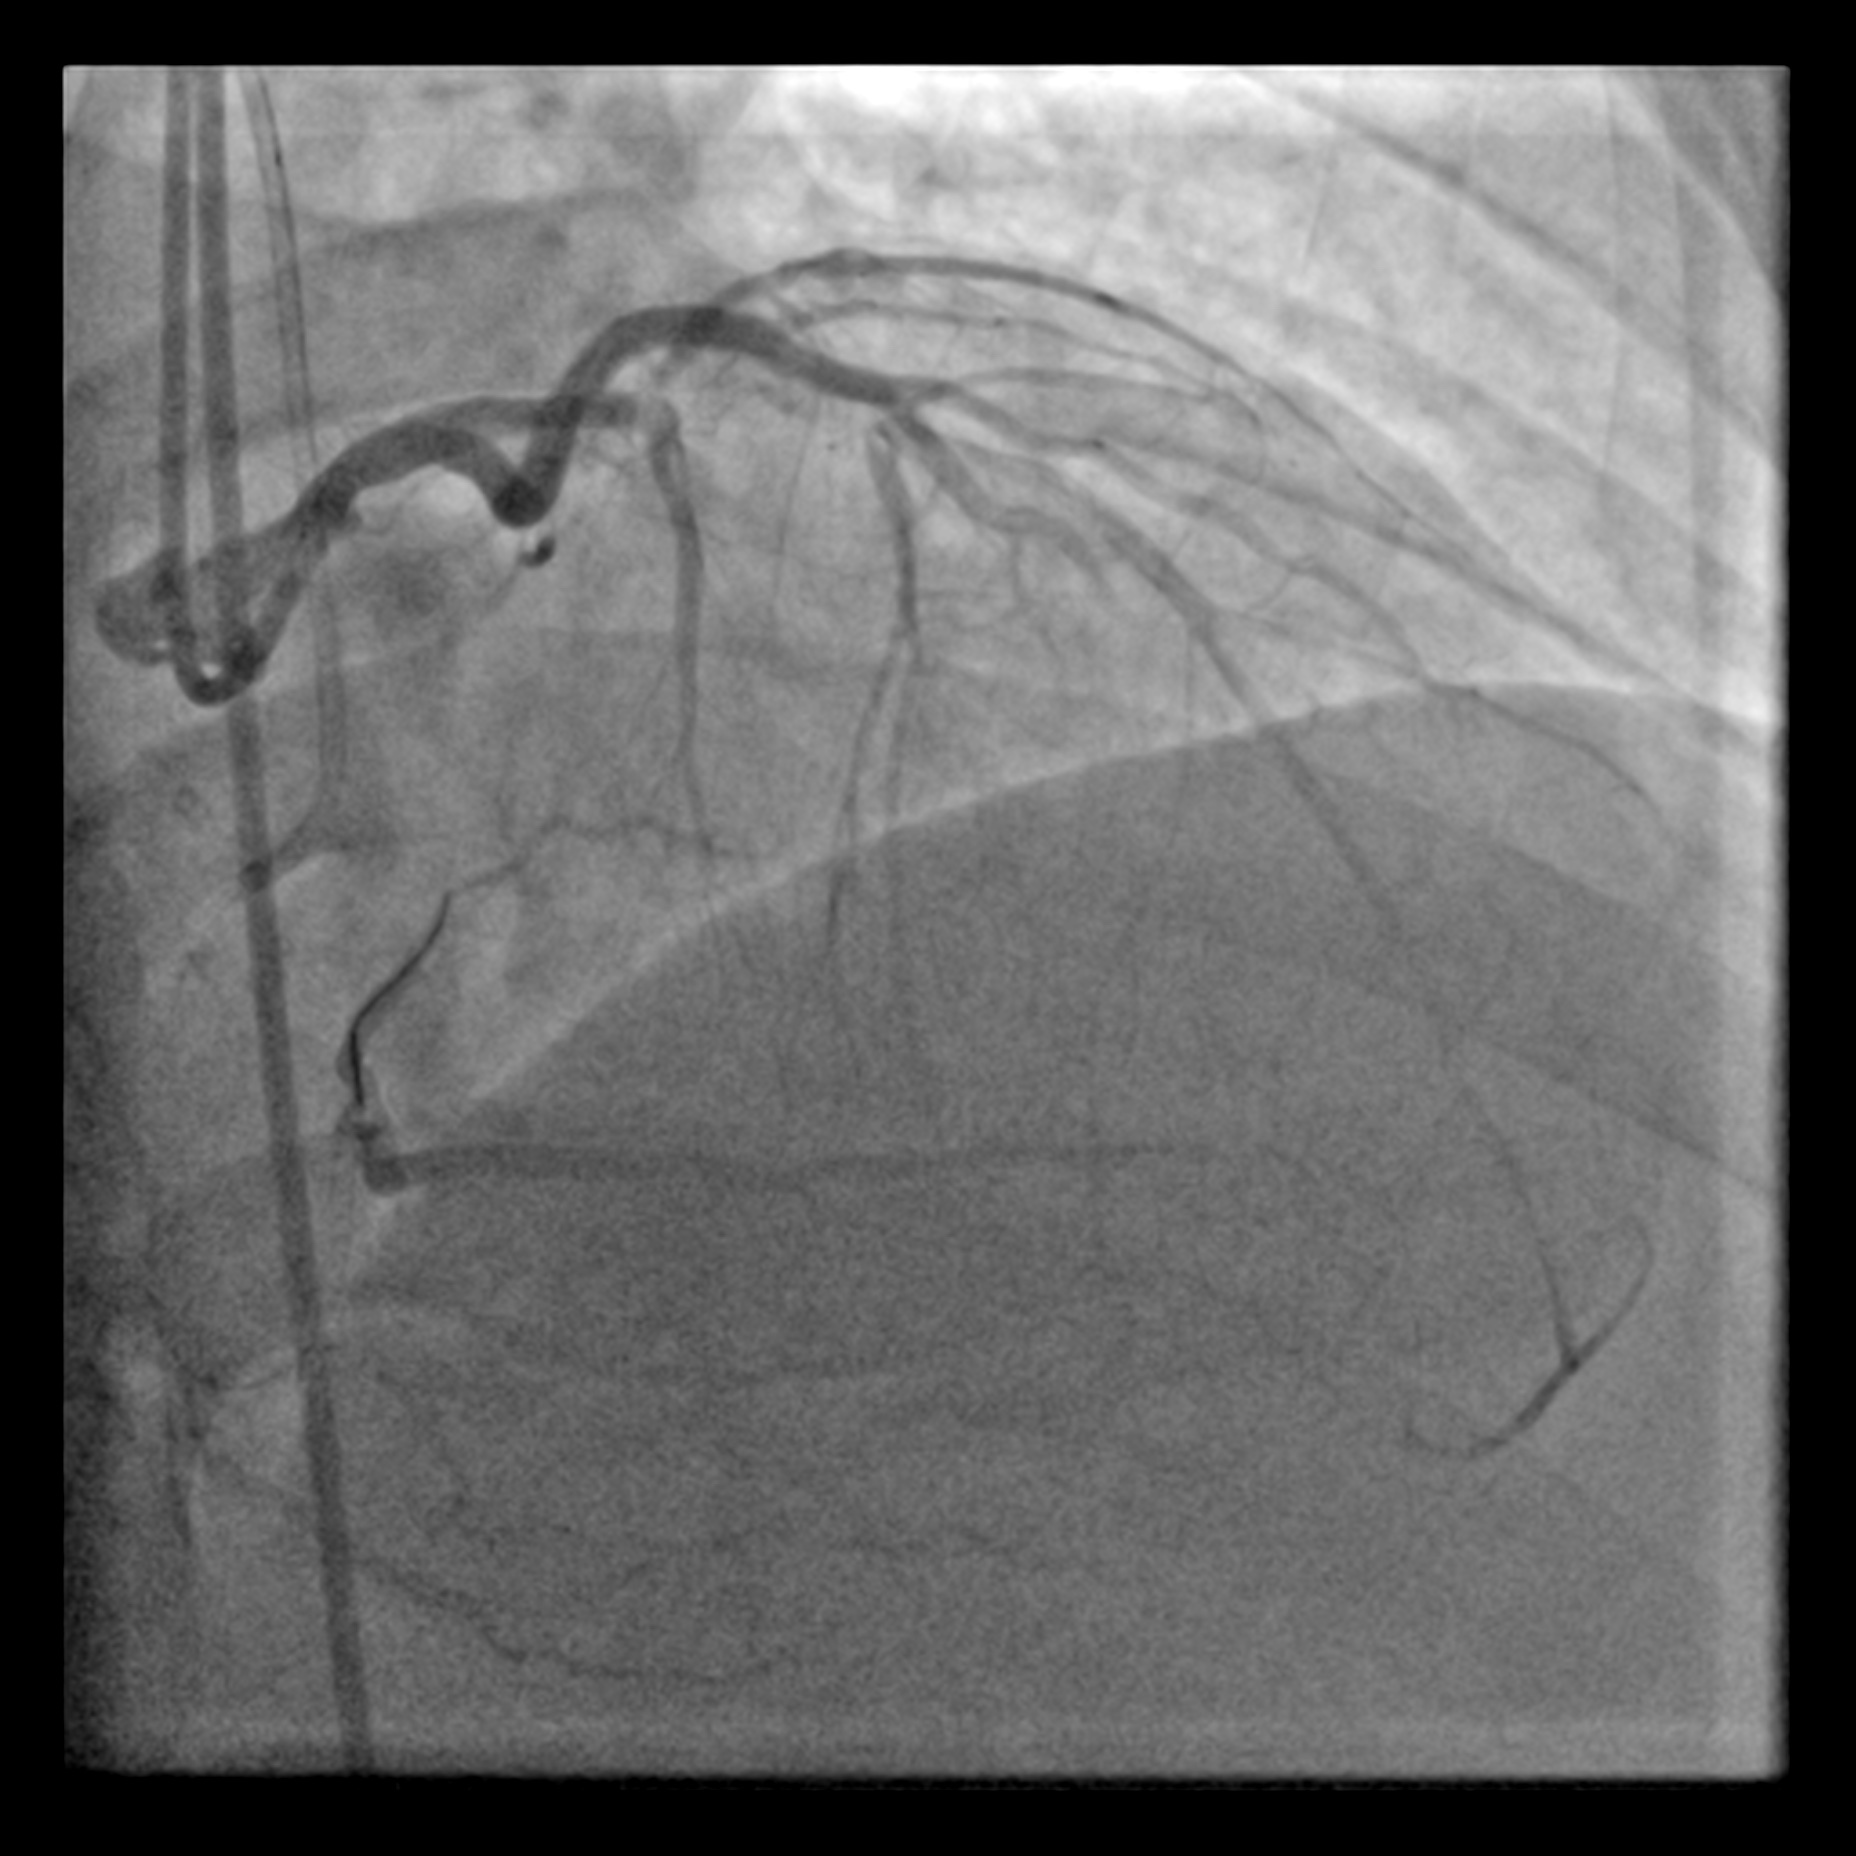

The proximal LAD demonstrates a Chronic Total Occlusion (CTO) with collateral flow from the Right Coronary Artery (RCA) via a septal perforator. The J-CTO score is 2, attributed to a blunt proximal cap and an estimated lesion length of more than 20 mm. The indication for CTO intervention is angina refractory to medical therapy. The procedure was planned using an antegrade approach via a 7 Fr EBU 3.5 catheter, with a contralateral injection from the RCA for visualisation.